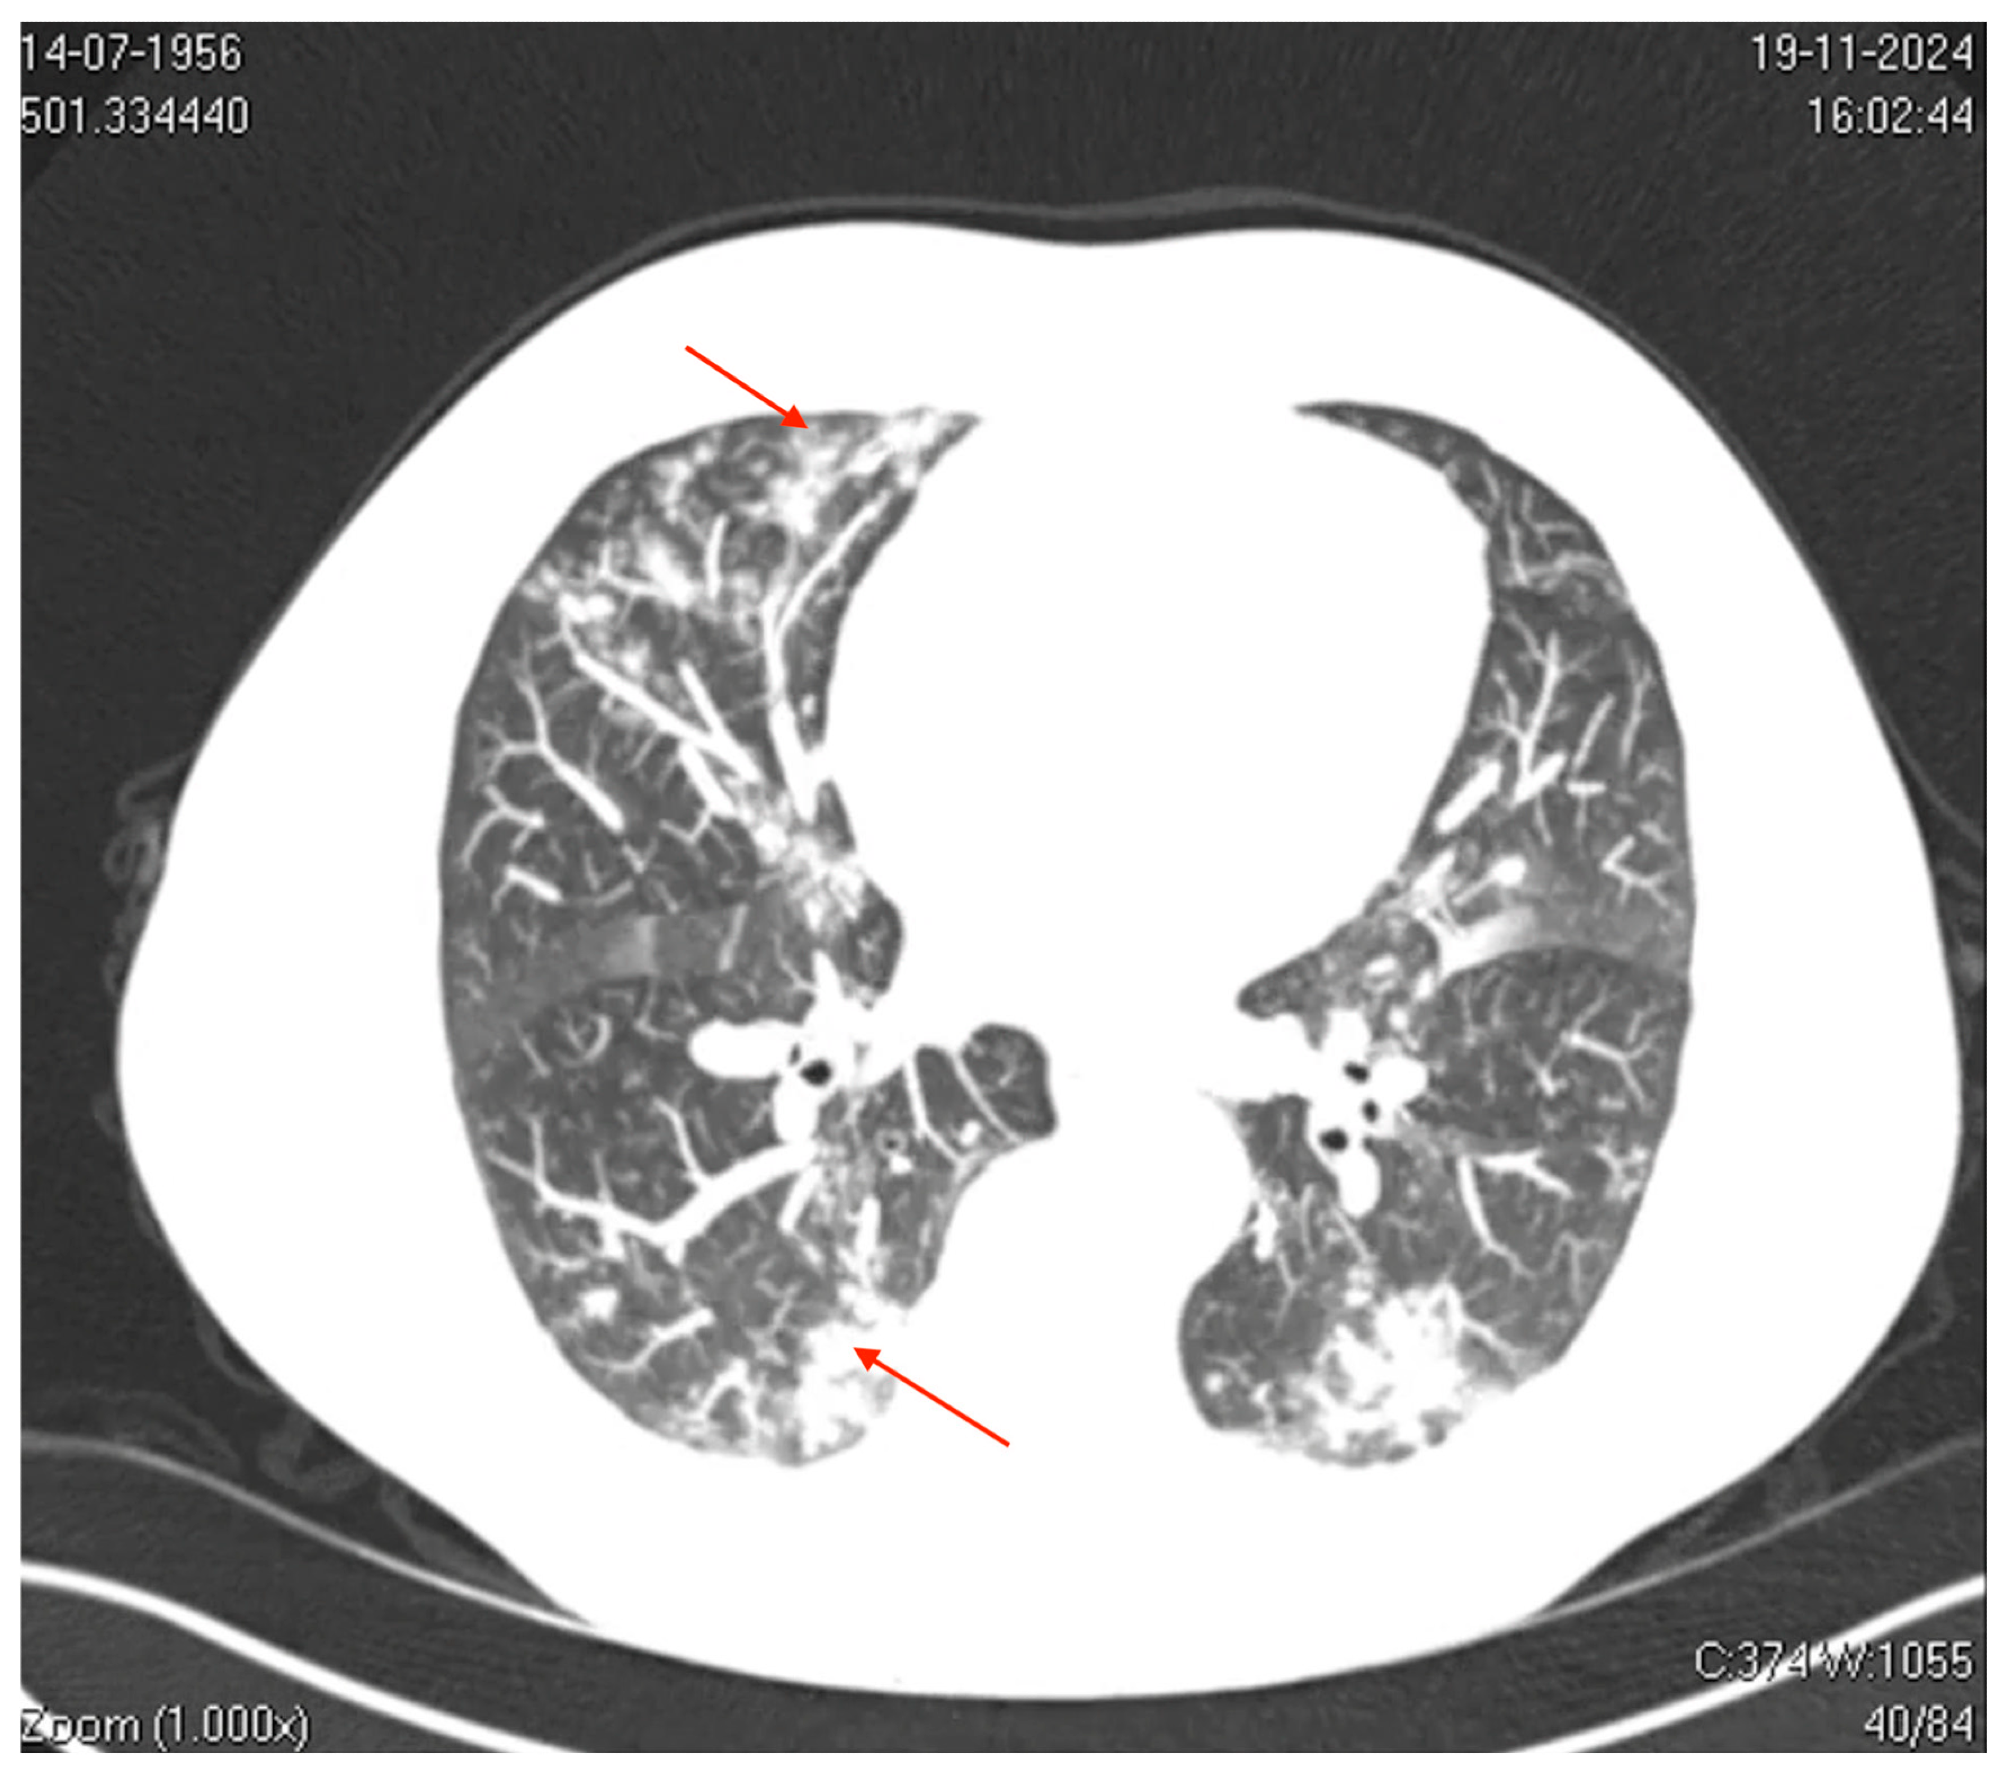

Axial computed tomography (CT) image of the thorax. The image shows bilateral ground-glass opacities with a reticular pattern interspersed with focal areas of consolidation and peripheral bronchiolar filling. The red arrows highlight specific areas of consolidation surrounded by ground-glass opacities, which are more prominent in the peripheral and lower lung regions. These findings suggest a diffuse inflammatory or infectious process involving the pulmonary interstitial and peripheral airways (acinus and bronchioles), which is consistent with viral pneumonia.

Thoracic computed tomography (CT) showed mild bilateral pleural effusions, ground-glass opacities interspersed with areas of consolidation, and small centrilobular opacities. These findings were consistent with a viral pneumonia pattern and predominantly affected the left lower and upper lobes. Besides, CT of the paranasal sinuses revealed mucosal thickening in the frontal sinus.

The present study underscores that hMPV can cause significant pneumonia in immunocompetent adults with no comorbidities. This highlights the growing recognition of hMPV as a frequent cause of CAP in different age groups, especially with the decline of bacterial infections. Radiological findings, such as ground-glass opacities and bilateral consolidations, are characteristic of viral pneumonia, further supporting the diagnosis. Notably, despite molecular testing revealing hMPV as the sole pathogen, antibiotic therapy was started, reflecting persistent diagnostic uncertainty in differentiating bacterial and viral infections.